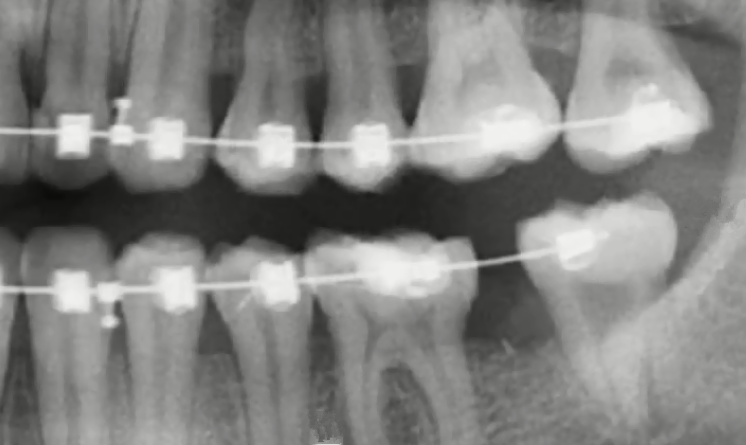

智齒牽引矯治

智齒如果牽引成功可以充當磨牙使用,結果是比較不錯的,而且如果注意認真刷牙和清潔口腔,好好保護,可以和其他牙齒一樣正常使用,但是由於(yu) 智齒是牽引過來的,為(wei) 了保持使用更長的時間,通常會(hui) 建議大家佩戴保持器的時間更長一些。

智齒牽引後